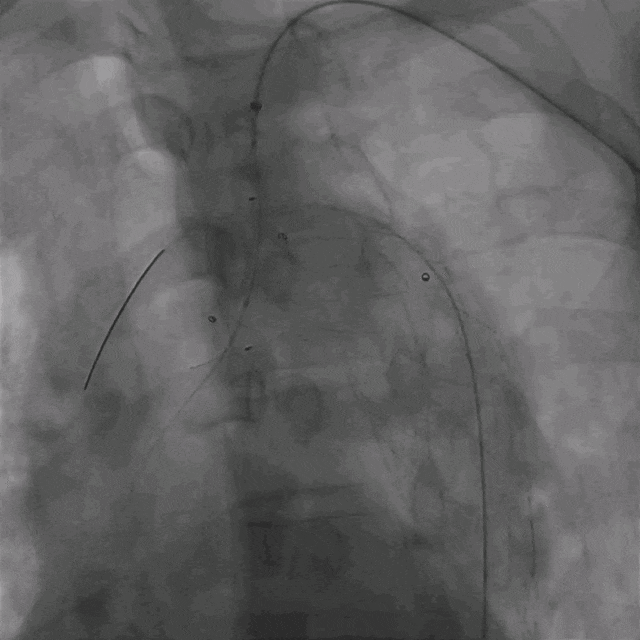

02. 交换0.035"Lunderquist超硬导丝至升主动脉,于左侧颈总动脉开口远端精确定位并释放华脉泰科PTBS3430180覆膜支架。造影提示主动脉溃疡隔绝完全,无内漏。

泥鳅导丝怎么用曲乐丰教授团队:0.018"和0.035"普通泥鳅导丝行胸主动脉弓上分支原位开窗的病例分享_https://www.jmylbn.com_新闻资讯_第9张

植入华脉泰科覆膜支架